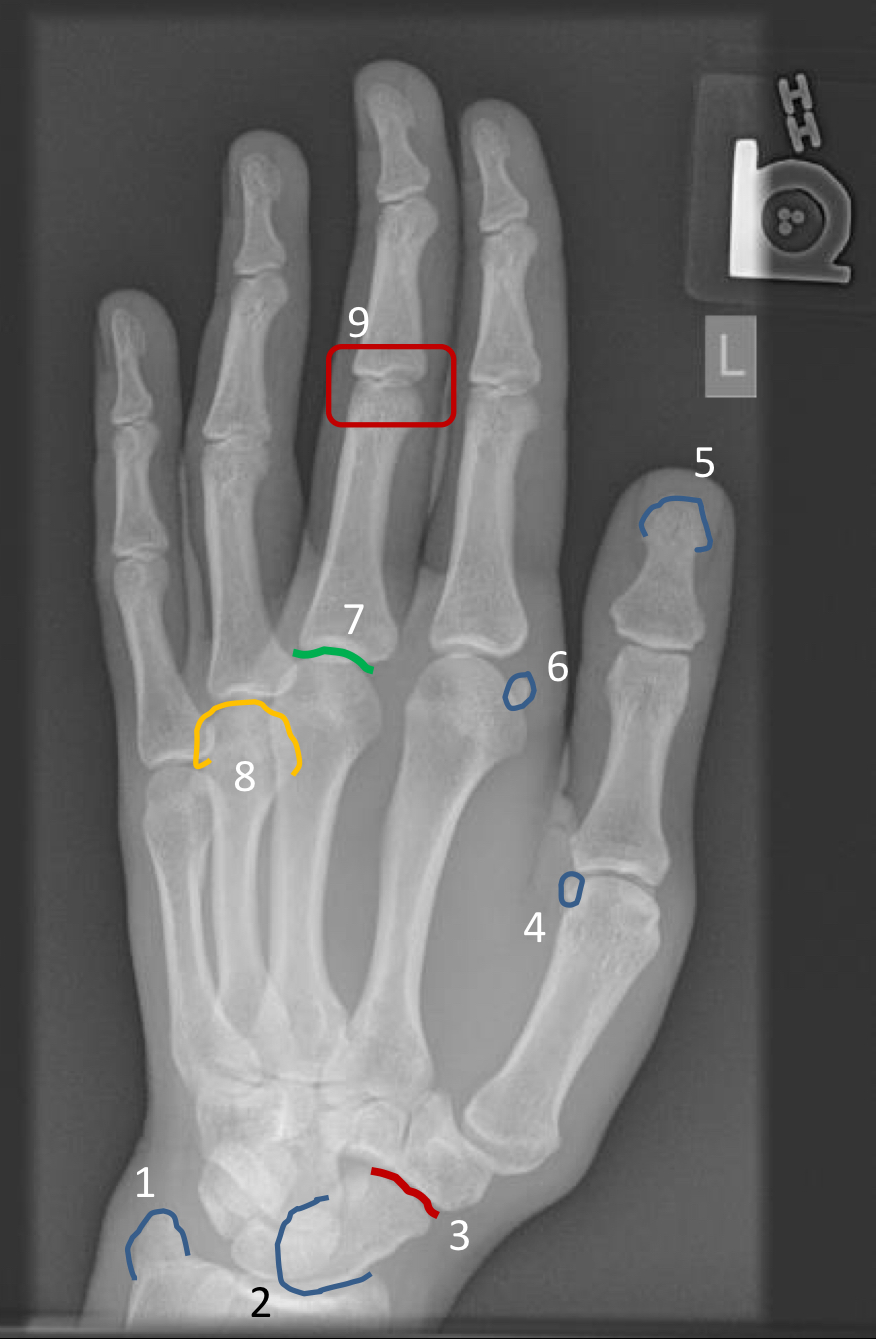

What view is this?

medial oblique

1?

ulnar styloid process

2?

proximal scaphoid

3?

scaphoid-trapezium joint space

4?

sesamoid at first metacarpal head

5?

1st ungual tuft

6?

sesamoid at 2nd metacarpal head

7?

3rd metacarpophalangeal joint space

8?

head of 4th metacarpal

9?

3rd proximal interphalangeal joint (not well visualized on oblique view)